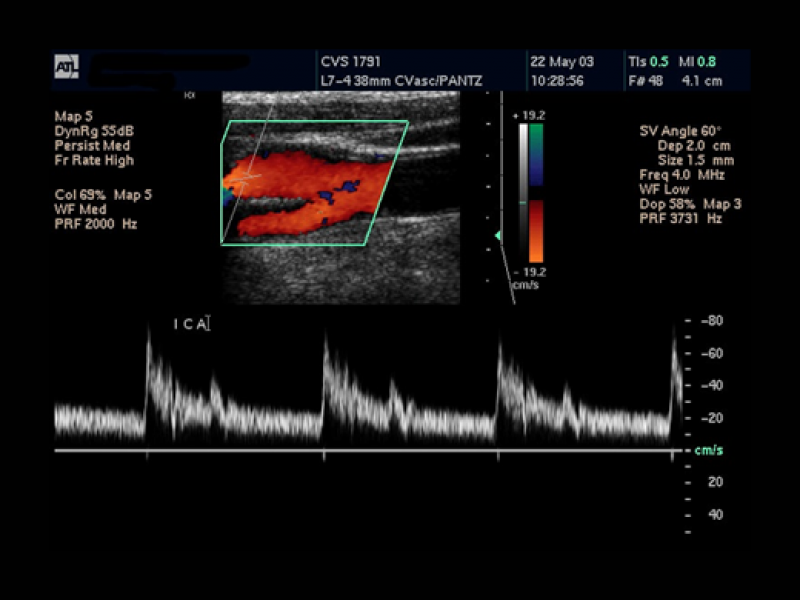

뇌에 혈액을 공급하는 혈관이 막히거나 터져서 뇌손상이 오고 그에 따른 신체 장애가 나타나는 뇌질환을 말합니다.